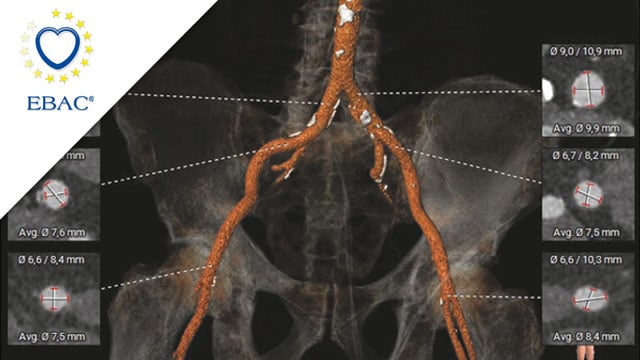

• AAA